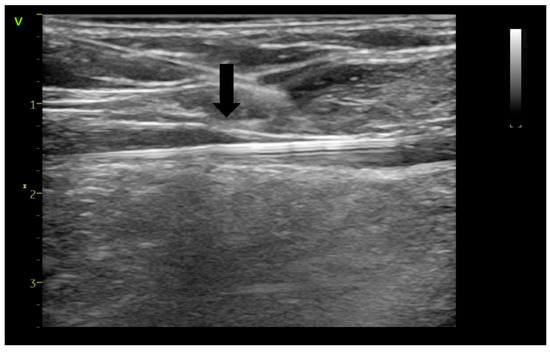

Assessing Endovenous Heat-Induced Thrombosis in Flush Endovenous Laser Ablation: A Study on Incidence, Risk Factors, and Patient Outcomes

J. Clin. Med. 2025, 14(17), 6165; https://doi.org/10.3390/jcm14176165 - 31 Aug 2025

Introduction: The introduction of radial-firing laser fibers has minimized catheter-to-vein distance during endovenous laser ablation (EVLA) for the great saphenous vein (GSV) and anterior saphenous veins (ASVs). This study investigates flush endovenous laser ablation (fEVLA) effectiveness in addressing chronic superficial venous insufficiency (CVI). [...] Read more.

Introduction: The introduction of radial-firing laser fibers has minimized catheter-to-vein distance during endovenous laser ablation (EVLA) for the great saphenous vein (GSV) and anterior saphenous veins (ASVs). This study investigates flush endovenous laser ablation (fEVLA) effectiveness in addressing chronic superficial venous insufficiency (CVI). Materials and methods: This single-center retrospective study analyzed consecutive fEVLA cases with duplex ultrasound follow-up at 1, 4, and 12 weeks. The primary endpoint was clinically significant endovenous heat-induced thrombosis (classes III–IV). Results: Three hundred and twelve patients were recruited (405 affected limbs, 369 GSV, and 36 ASV). CEAP classifications were stratified as follows: C2 in 6.1%, C3 in 34.2%, C4 in 44%, C5 in 2.7%, and C6 in 12.7% of cases. Perforator ligation, phlebectomy, or foam sclerotherapy were carried out in conjunction with EVLA. fEVLA was feasible in all cases. The success rate was 96.78%, defined as EHIT classes 1 and 2, and assessed by ultrasound one week postoperatively. Clinically significant EHIT (2.5% class 3 and 0.2% class 4) was managed with 15 mg rivaroxaban twice daily for 21 days. Follow-up at 4 weeks revealed complete resolution of all EHIT 3–4 cases. No cases of pulmonary embolism or deep vein thrombosis were observed during the study or follow-up period. Conclusions: fEVLA is a safe treatment for superficial CVI across various CEAP classes, and with prompt detection, the minimal complication rate can be completely resolved. Full article

Show Figures

Figure 1